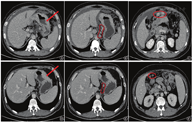

患者男,43岁。3个月前无明显原因出现腹胀,偶有上腹部隐痛不适,间断黑便,无恶心、呕吐,未在意,后腹胀进行性加重,就诊于当地医院,2018年12月7日行胃镜检查提示:胃体狭窄,狭窄段黏膜粗糙不平,局部隆起胃窦黏膜点片状红斑。病理提示:低分化腺癌。患者为求进一步诊治来我院,门诊以"胃癌"收入胃结直肠外科。辅助检查:腹部CT(图1)提示胃体占位,考虑胃癌;腹膜、网膜弥漫性增厚,考虑转移;腹腔积液。CT分期考虑cTNM:T4aN2M1。

注:图A箭头标志处为肿瘤、腹腔积液及肿大淋巴结;图B箭头标志处为增厚网膜